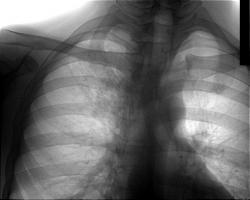

Пациенту за 30, жалоб нет, профосмотр, что-нибудь видите?

Ага, мне тоже! по прямому снимку просто таки - центральный c-r в/доли правого легкого с мтс в бронхопульмональные и трахеобронхиальные л/узлы. Еще как вариант - лимфопролиферативное заболевание (лимфогранулематоз?), саркоидоз

Разве изменение рисунка в верхушке и под ключицей (усиление, нечеткость с инфильтративным компонентом) не лучше видны на косых? Уж по крайней мере они подтверждаются. В чем Наталия была первой? Она что-то про корень писала, важнее все-таки изменение рисунка, учитывая локализацию, можно сделать вполне определенное предположение.

Да, изменения легочного рисунка видны лучше на косой, тем не менее они видны и в прямой проекции... Кроме того есть расширение правого корня и затемнение правого трахеобронхиального угла, что также важно и игнорировать нельзя, а для этих двух симптомов боковая рентгенограмма и томография (линейная или компьютерная) дали бы больше информации, чем косой снимок, т.к. можно еще выявить объемное уменьшение, узловое образование, сужение бронха и т.д.

С точки зрения врача с глубокой периферии использовал-бы именно стандарт - Прямая + правая боковая. С учетом наличия очаговых теней справа в верхней доле (верхушка), безоговорочно произвел-бы линейную томографию в стандартных срезах, и возможно, с определенной степенью вероятности, выявил-бы "тубарь", возможно ошибаюсь, по поводу диагноза, но не ошибаюсь по поводу "стандарта".

Тянет на инфильтративный туберкулез S1-S2-S3 правого легкого.

Звонил в ТД, оказывается делал КТ - инфильтративный беркулез.